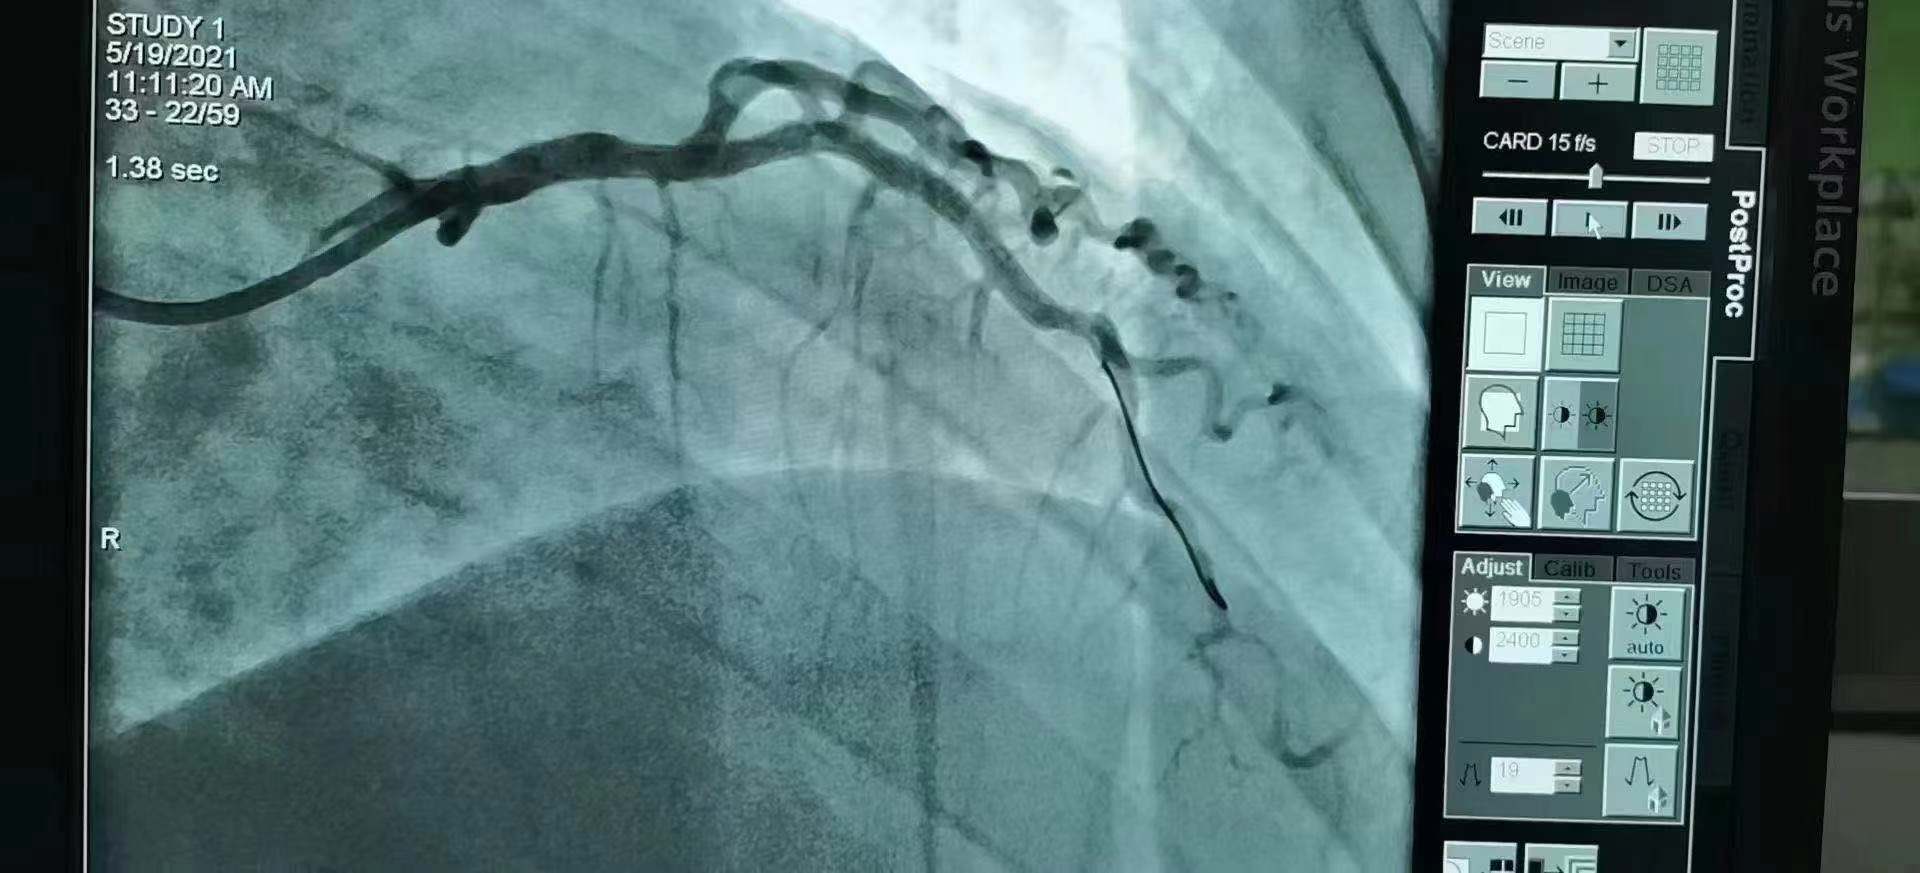

青島市第三人民醫(yī)院 李曉主任團(tuán)隊成功為患者植入Xinsorb生物可吸收支架!

祝賀 青島市第三人民醫(yī)院  李曉主任團(tuán)隊成功為患者植入Xinsorb生物可吸收支架!